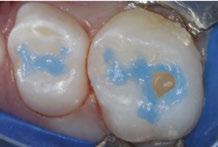

The 5-year-old patient featured in this case study did not benefit from early oral care and had multiple carious lesions. Considering the young age, high caries risk, and the uncertainty of compliance with follow-up appointments, I wanted to restore and seal all teeth in one visit. One quadrant is shown in this case study. The carious lesion on tooth J (65) was cavitated and prepared, restored, and sealed. Tooth I (64) was non-carious and would only be sealed (Figure 1).

Tooth J (65) was prepared with a coarse tapered high-speed diamond bur allowing for some minor mechanical retention by incorporating minimal undercut in preparation. The occlusal

surface of tooth I (64) was also lightly abraded with a diamond bur (Figure 2). The preparations were selectively etched with phosphoric acid, rinsed, and lightly dried (Figure 3). Bonding agent was applied to the entire occlusal surfaces of both teeth, air thinned, and light-cured (Figure 4).

Tooth J (65) was bulk-filled with Activa Kids. For this fast injection technique, I place the dispensing tip at the floor of the preparation and extrude the material without removing the tip until the preparation is completely filled (Figure 5). I like to do some minor manipulation of the filling material with hand instruments to create anatomy, as well as to ensure the material is flush with the surface of the preparation, and no air is trapped inside. Activa Kids is dual-cure, ideal for bulk filling, and can be cured with all lights. A thin topcoat of Activa Presto was placed as a sealant on the entire occlusal surface of teeth I and J (64 and 65) (Figure 6). Figure 7 shows the final clinical situation.

Figure 1 (left): Caries lesion on tooth J (65). Figure 2 (center): Preparation of tooth J (65) and abraded occlusal surface of tooth I (64). Figure 3 (right): Selective etch of enamel Figure 4 (left): Bonding agent is applied to both teeth I and J (64 and 65). Figure 5 (right): The preparation is filled with ACTIVA Kids Figure 6 (left): A thin topcoat of ACTIVA Presto is applied to the occlusal surfaces of teeth I and J (64, 65). Figure 7 (right): Final result